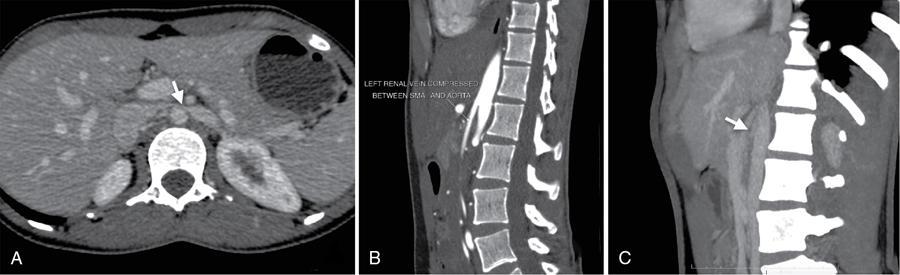

• Look for features of ‘Nutcracker syndrome’ (Fig. 10.18.1.2) – it is characterized by compression of left renal vein between aorta and proximal superior mesenteric artery resulting dilated prestenotic segment and left ovarian/left parauterine veins.

Fig. 10.18.1.2 CT image for nutcracker syndrome.